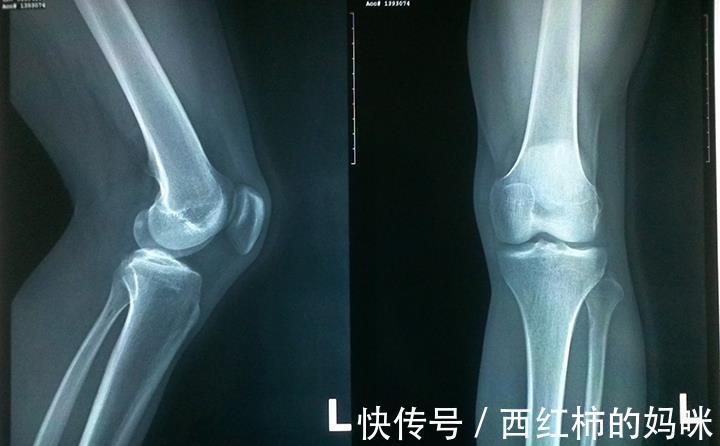

文章插图